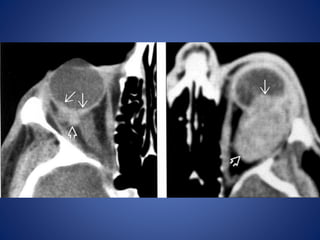

• #5 Ocular rupture. Axial CT scan shows deformity of the left eye with uveoscleral infolding due to ocular hypotony related to a rupture.

• #6 Ocular trauma and choroidal hematoma. Axial CT scan shows a hyperdense left choroidal hematoma. This can be confused with a choroidal melanoma.

• #7 Choroidal hematoma following ocular surgery. Axial CT scan shows multiple choroidal hematomas of various sizes involving the left eye.

• #8 Perforation and collapse of the globe. posterior aspect of the globe, Axial CT scans show infolding (arrowheads) of the posterior aspect of the globe, and the lens (arrow) is partially displaced.

• #9 A, Axial CT scan shows the intraocular lens (arrow) on the right side. Left globe has lost tone and has partially collapsed, with infolding of the posterior sclera. B, Sagittal reconstruction shows the displacement of the lens (arrowhead) into the posterior aspect of the vitreous compartment.

• #10 Acute perforation of the globe on the right side. Phthisis bulbi and calcified lens on the left side. There is inward buckling of the sclera of the right globe after acute trauma. There is calcification along the wall of the globe on the left, with a calcified lens (arrow) from a previous insult.